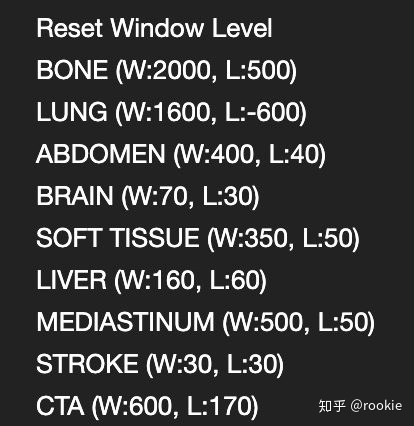

return Hu(2)获得HU为单位的图像的矩阵后,需要针对HU图像进行调窗,以适应于我们对不同部位的图像进行分析(医学图像中不同部位的适用的HU范围不同,这个范围叫做窗口),在imageJ中窗口的大小叫做window,窗口的中心叫做level,在这几个参考的帖子中有不同的叫法,在此按照ImageJ 的名称[5,6]。

return norm_调窗后的数据就是想要查看的数据范围了,在这里对不同部位调窗的数据值设定也不相同[7].